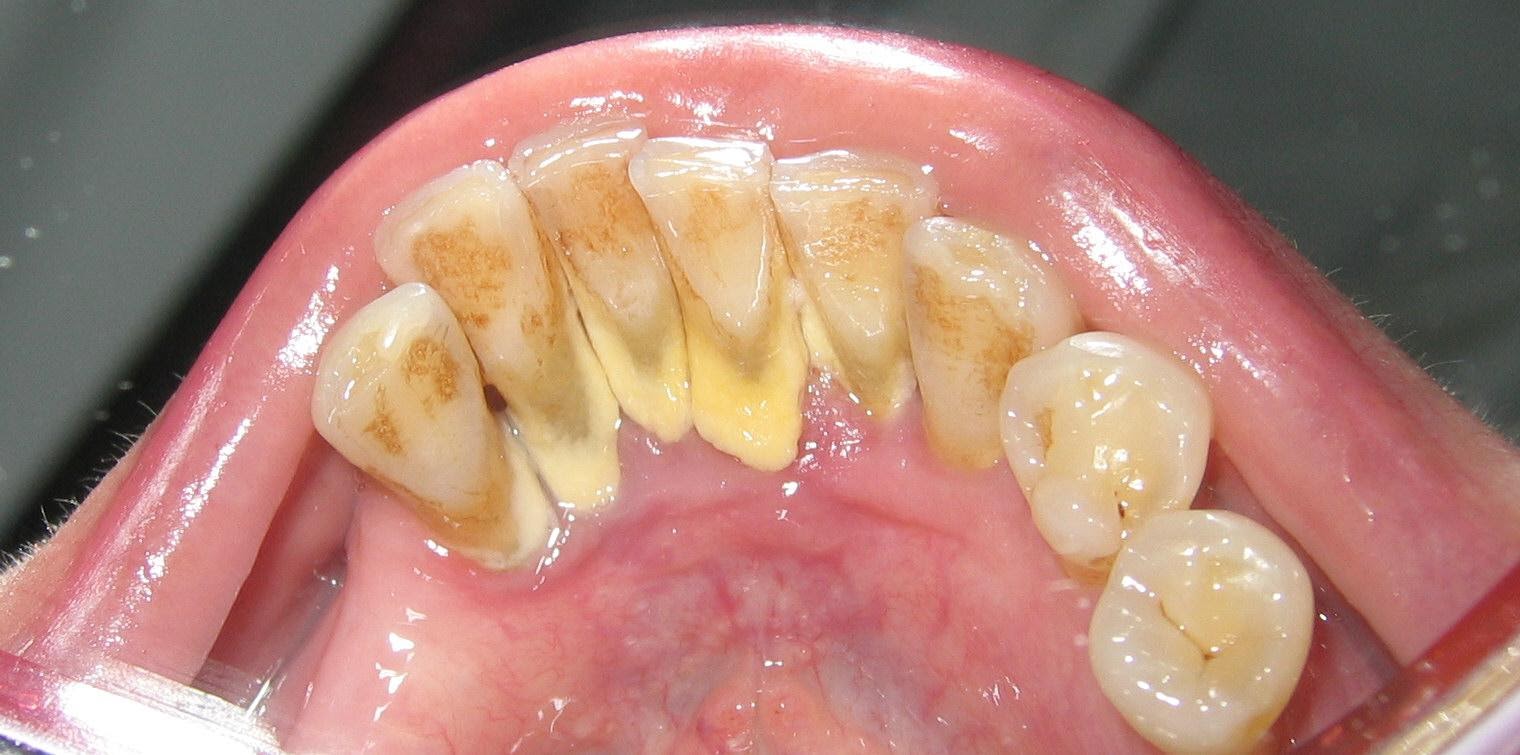

Зубной камень. Часто незаметный для носителя. Убрать можно только у стоматолога.

Зубной камень (зубная бляшка) — это намертво прилипший к зубам и тканям десневой борозды твёрдый минерализованный конкремент. Процесс формирования идёт постепенно. Начинается всё с того, что у вас из-за неправильного прикуса, неудачных ортопедических или ортодонтических конструкций или из-за плохой гигиены начинает скапливаться зубной налёт в области десны. Где-то через два–четыре часа на поверхности ваших зубов начинают десантироваться первые бактерии, которые быстро формируют пелликулу — плёнку из органических молекул и микроорганизмов. Дальше бактерии начинают прикрепляться ко всем шероховатым участкам эмали, где их не смывает немедленно слюной. Многие бактерии неспособны сами прикрепляться к эмали и ждут, пока другие не сформируют посадочную площадку. В итоге возникают причудливые структуры в виде кукурузных початков из круглых кокков вокруг нитевидных бактерий.

Зубной камень. Дома отодрать можно разве что плоской отверткой, но делать так не надо.

Когда я говорю, что пациент не может сам удалить зубной камень, у него в глазах часто прям загорается фрагмент с Барни и его фразой «Challenge accepted». Реально был случай, когда пожилой мужчина решил, что по таким вопросам стоматологов беспокоить не стоит, и старательно снимал зубной камень маникюрными ножницами. Через год всё равно пришёл, но уже с множественными травмами и микроповреждениями дёсен.

На самом деле при хорошей гигиене зубной камень не превращается в ужасающую кальцифицированную монопластину, как челюсть у черепахи. Камешки небольшие, аккуратно себе лежат под десной и медленно разрушают пародонт. При этом сами зубы могут быть красивыми, ухоженными и без кариеса. Видно их только стоматологу, который со своими зеркалами и микроскопами может подлезть в самые далёкие уголки вашей полости рта.